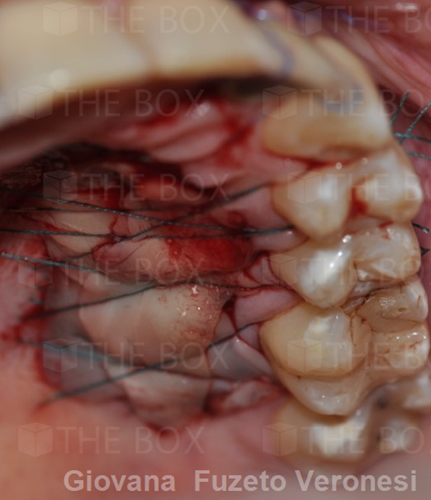

Infra bony defect one wall defect follow up 18 months show regeneration of buccal bone and interdental defect utilizing allograft bone substitute